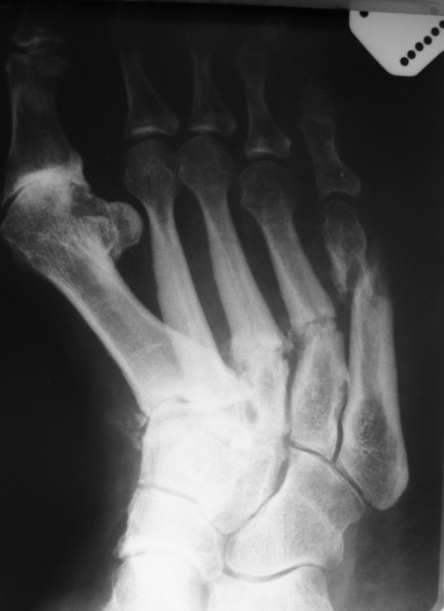

Уважаемые коллеги. Помогите определиться с дальнейшим лечением данного клинического

случая (Ро - граммы прилагаю ). Жалобы: На постоянные боли в области обеих стоп,

преимущественно справа в покое и при осевой нагрузке. Невозможность ходить на длительне

дистанции. Из анамнеза: Со слов больной травмы отрицает. Считает себя больной последние 5

лет, когда в первые появились боли в стопах и правом тазобедренном суставе. Обращалась в РТП

по месту жительства, выполнялись Ро - граммы ( на руках ), без патологии. болевой синдром

постепенно наростал. Пациентка лечилась консервативно по месту жительства с переменным

успехом. Выполнялись этапные Ро - контроли ( к сожалению Ро - утерян в РТП ). Со слов пациентки

Ро - картина ухудшалась. Данное ухудшение с февраля 2009 года. больная стала отмечать

отрицательную динамику, появилось искривление области плюсны по тыльной поверхности

стопы, крепитация отломков, усиление болевого синдрома, отёк в области правой стопы,

формирование экзостоза головки 1 плюсневой кости, уплощения продольного свода стопы,

невозможность носить ежедневной обуви ( в плоть до домашних тапочек ). и вот она измученная

лечением обратилась к нам...Трудовой анамнез не отягощён. Работает поваром в столовой.

Местно: У больной имеется отёк мягких тканей тыла стопы. при осмотре продольный и поперечный

своды стопы уплощены. имеется вальгусная деформация 1 го пальца правой стопы. Экзостоз

головки 1 плюсневой кости. Кожа над поверхностью не изменена. признаков гипертермии и

гиперемии нет. При пальпации отмечается болезненность в проекции диафизов 2-4плюсневых

костей по тыльной поверхности. Так же отмечается крепитация отломнов в проекции 5 плюсневой

кости. Признаков сосудистых и неврологических расстройств нет. При стоянии на обеих ногах,

отмечается болезненность в проекции 5 плюсневой кости правой стопы. У нас возник извечный

вопрос...Что делать?